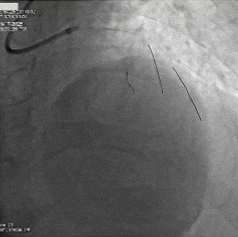

手术过程:

术后造影

术中造影提示第一、第二对角支开口严重狭窄,分别对前降支严重钙化病变、回旋支次全闭塞应用OAS进行旋磨等充分预处理后,导丝顺利通过病变,成功植入支架、药物球囊,实现血管再通,术后患者血流恢复良好。